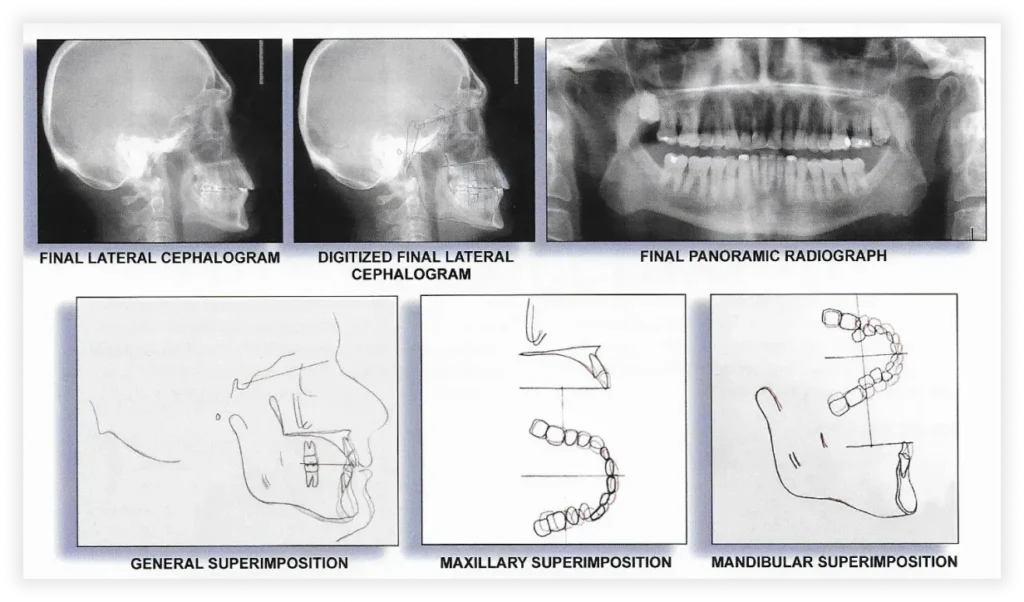

Smile Gallery

Take a look at some of our cases and successful transformations below.

Case #1

Initial Photos

Final Photos